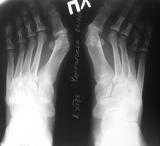

Уважаемые коллеги! Обратилась болная с жалобами на боли в стопе.

В 1989 году перенесла операцию по поводу HV - очевидно была сделана операция по Шаде. Сейчас беспокоят боли в стопах, продолжается вальгизация пальца, натоптыши на подошвенной поверхности. Ваше мнение об объеме операции. Заранее благодарю Сергей Киселев.

ПОСЫЛАЮ Р-ГРАММУ

Кликните для загрузки файла ФОРУМ1.jpg

Юрий Александрович, плюсне-фаланговое сочленение - 38 градусов, угол между I-II плюсневыми костями - 14 градусов, меду I-V плюсневыми костями - 28 градусов. Это поперечно-распластанная деформация III степени.